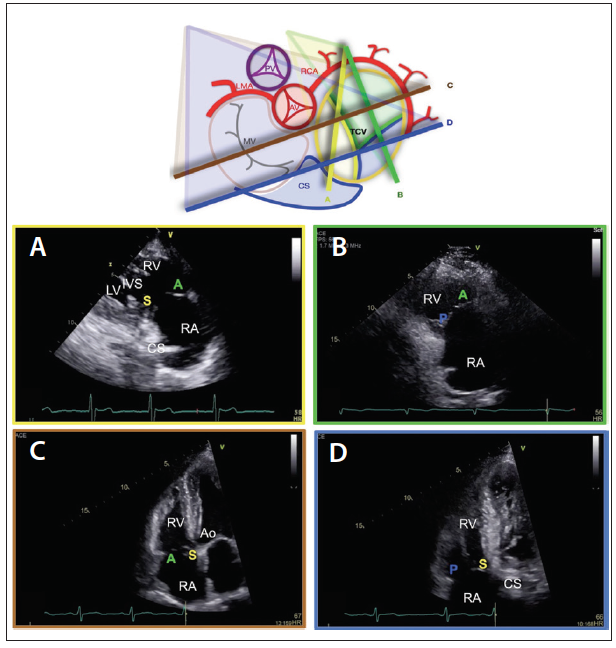

The parasternal RV inflow view allows for consistent visualization of the anterior leaflet in the near field, whereas the far-field leaflet can either be the septal leaflet (if the coronary sinus and/or the interventricular septum is visualized) or the posterior leaflet (if the coronary sinus and the interventricular septum are not visualized as the transducer is rotated rightward with inferior angulation) (Figure 2A and 2B).4,22 The parasternal short-axis view captures the anterior leaflet that might either be visualized alone, with the posterior leaflet (especially if the tricuspid valve annulus is dilated), or with the septal leaflet (if the transducer is angled toward the left ventricular outflow tract) (Figure 3).4,22

Figure 2. Schematic of the TV as viewed from the RA and the correlating TTE parasternal RV inflow view and apical four-chamber view. In the parasternal inflow view, if the CS and/or the IVS are visualized then the leaflets demonstrated are the A and S leaflets (panel A). In the same view, if the transducer is rotated more rightward and inferiorly, the CS and IVS will disappear and the leaflets imaged are the A and P leaflets (panel B). In the apical view, when the transducer is angled anteriorly, the Ao, the S and A leaflets are imaged (panel C). In this view, if the transducer is angled inferiorly and the CS is visualized, the leaflets that are imaged are the S and P leaflets (panel D). A, anterior leaflet; Ao, aorta; AV, aortic valve; CS, coronary sinus; IVS, interventricular septum; LMA, left main artery; LV, left ventricle; MV, mitral valve; P, posterior leaflet; RA, right atrium; RCA, right coronary artery; RV, right ventricle; S, septal leaflet; TTE, transthoracic echocardiography; TV, tricuspid valve.

The other important imaging plane is the apical view, which consistently shows the septal leaflet (adjacent to the interventricular septum) with the opposing leaflet being the anterior leaflet (if the transducer is angulated anteriorly, showing the aorta) or the posterior leaflet (if the transducer is angulated posteriorly, showing the coronary sinus) (Figure 2C and 2D).4,22